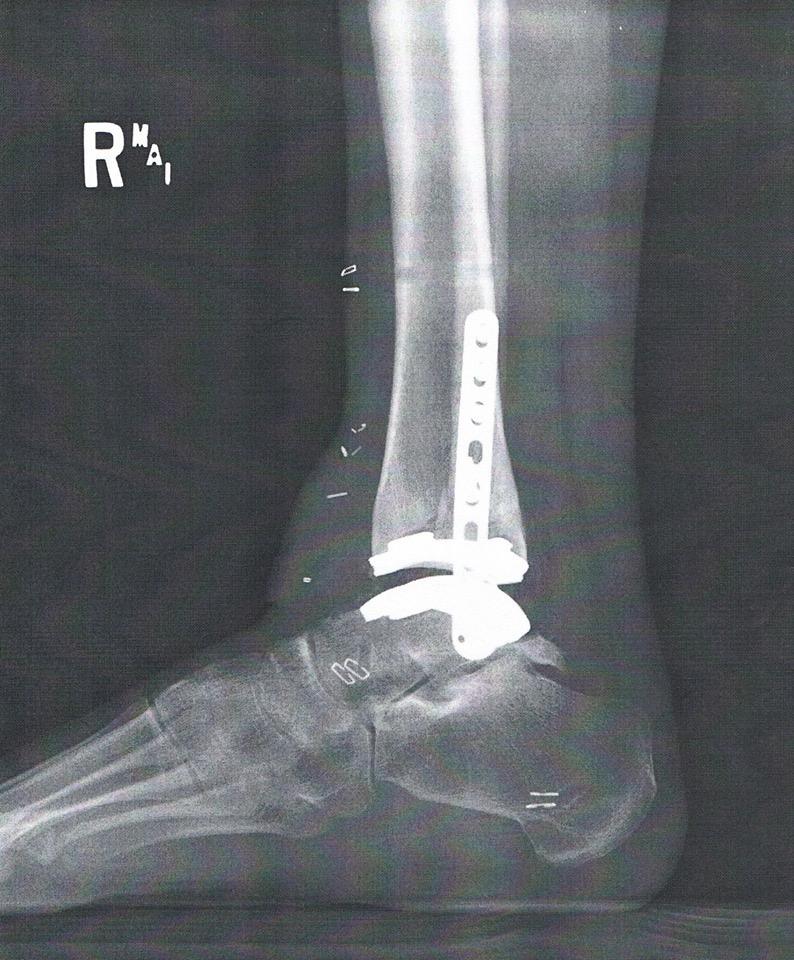

An ankle replacement. I have one. I received mine at age 30 and I’m currently 39. Was it a good decision or bad decision?

Never skip the fine print (which is located here). Since I recommend not skipping this nugget of gold I’ll keep the font size readable… God did not create ankle replacements. Man did. Sure you can argue (and I’ll agree) that God helped man create ankle replacements but that is a conversation for a different article. My ankle replacement is NOT a perfect substitute for a young ankle that hasn’t sustained injuries. My ankle replacement has limitations (mostly range of motion); however, it has eliminated constant pain that camped out on the upper end of the pain scale. It is important to further note: my lack in range of motion doesn’t necessarily mean it is an issue with the ankle replacement. I had issues with my Achilles tendon, which Dr. Conklin lengthened during my ankle replacement surgery, and I’m not convinced I don’t have a bone spur that the replacement is catching on. It isn’t bad enough to warrant surgery so I’m continuing with my life. Side note: even after my injury I had great alignment which opened the conversation of ankle replacements in the first place.

Zimmer Biomet Ankle Replacement (the ankle replacement I received)

adrienne bulinski ankle replacement.jpg